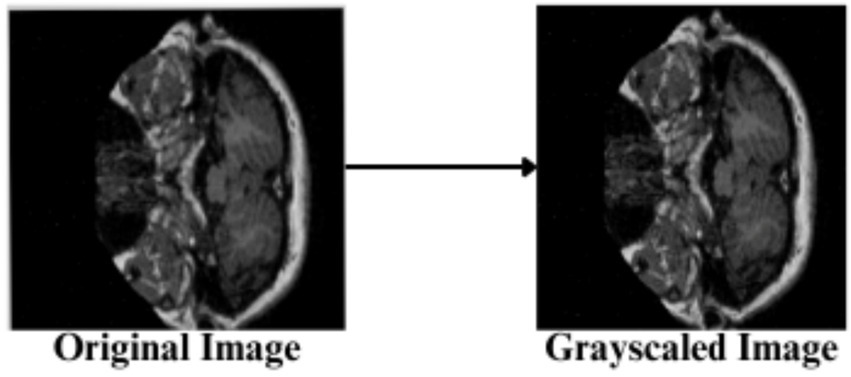

The feature engineering process for this study is to process and augment MRI image data so that relevant patterns associated with Alzheimer’s Disease can be captured. All images are resized to 256 × 256 pixels so that input size is standardized for neural networks, and the same is done to ensure all images have uniform dimensions in order to train the model. It reduces computational complexity, making the processing faster. The next step makes use of image augmentation techniques with the training set, thus artificially increasing the model’s capabilities to generalize new yet unseen data. These techniques include brightness alterations, horizontal and vertical flips, zoom, rotation, and shearing. Horizontal and vertical flipping was performed with 50% chance, and rotation was done clockwise, counter-clockwise, and upside down at random. Cropping was used with a zoom from 0% to a maximum of 4%. Rotation in the −1° to +1° range was used, and shearing transformations were used with ±2° shears in the horizontal and vertical directions. 10% of the images were processed by grayscale conversion and hue adjustment ranging from −15° to +15°, saturation from −25 to +25%, and brightness ranging from −10 to +10%. Those transformations are able to replicate somewhat real-world variations or imperfections that might take place in MRI scans, like different patient positions, variations in lighting, and some variations in the quality of the scan. These techniques help it learn to recognize the patterns related to disease under different conditions and be more robust to variations in the data. Figures 3–9 visually depict the feature engineering operations utilized in this study.

Feature engineering—grayscaling of image.

3.3.4 Image gray scaling

10% of the input images are converted to the Grayscale range, shown in Equation 6, utilizing the RGB values combined into a single luminance.